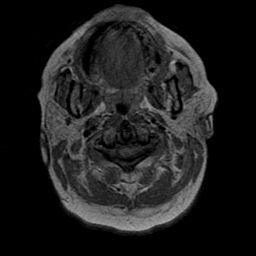

Cerebral hemorrhage, MR Study mr-pd -- Slice #0

[Home][Help][Clinical] Slice 0